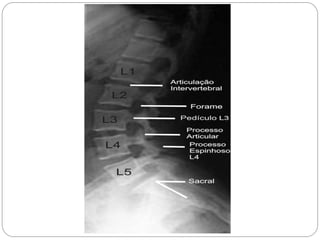

Vértebra lombar

Os corpos vertebrais são maiores, apresenta o forame vertebral em forma triangular e processos mamilares. Pode ser diferenciado também por não apresentar forame no processo transverso e nem a fóvea costal.

ASPECTOS GERAIS DA VERTEBRA LOMBAR

Os corpos vertebrais da região lombar possuem a forma de um rim.

Cada corpo vertebral possuem margens laterais côncavas e anteriores convexas

Sua dimensão transversa de cada um excede sua dimensão ântero-posterior

Vértebra lombar Oscorpos vertebrais são maiores, apresenta o forame vertebral em forma triangular e processos mamilares. Pode ser diferenciado também por não apresentar forame no processo transverso e nem a fóvea costal.

ASPECTOS GERAIS DAVERTEBRA LOMBAR Os corpos vertebrais da região lombar possuem a forma de um rim. Cada corpo vertebral possuem margens laterais côncavas e anteriores convexas Sua dimensão transversa de cada um excede sua dimensão ântero-posterior